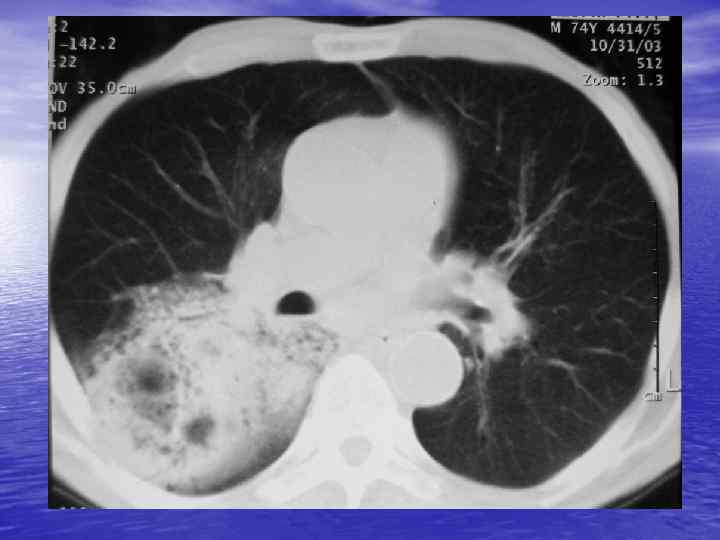

Денситометрический анализ Определение основных видов патологических образований: - обызвествленных - мягкотканных - жидкостных - жиросодержащих - воздухсодержащих

Электронные окна üОкном (Window) называют определенную часть шкалы Хаунсфилда, которой соответствует перепад величины яркости экрана от белого до черного. üШирина окна (Window Width, WW) — это величина разности наибольшего и наименьшего коэффициента ослабления, отображаемых данным перепадом яркости от белого до черного цвета. üУровень окна (Window Level, WL) — это величина коэффициента ослабления, соответствующая середине окна. Изменение уровня окна позволяет перемещать его в сторону больших или меньших значений чисел Хаунсфилда.

Характеристика основных электронных окон Электронное окно WINDOW Уровень окна Ширина окна Мягкотканное Soft +40 500 Легочное Lung -800 1000 Плевральное Pleural -650 -150 1500 -2000 Костное Вone +150+350 1000 -2000

Преимущества спиральной КТ: ü Возможность проведения исследования с болюсным ü ü ü ü ü контрастированием Высокая разрешающая способность; Высокая скорость исследования; Получение высококачественных изображений костных структур; Возможность обследования всего тела; Возможность проведения исследования больных под наркозом; Возможность детальной оценки состояния крупных и периферических сосудов в условиях искусственного контрастирования; Высокая информативность метода при черепномозговых травмах в остром периоде; Ранняя диагностика ишемических и геморрагических инсультов; Метод выбора для диагностики заболеваний легких; Планирование лучевой терапии.